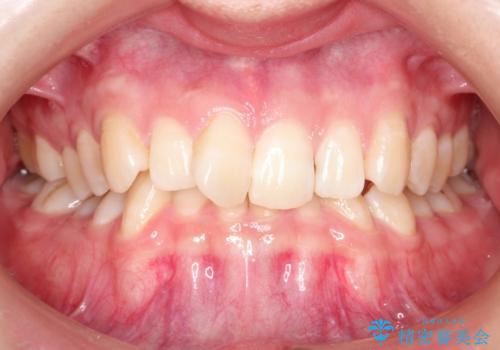

ハーフリンガル ワイヤー矯正による非抜歯・過蓋咬合の治療

- 20代女性

- 非抜歯、大臼歯遠心移動による臼歯関係の是正・過蓋の改善をハーフリンガル・ワイヤー矯正にて計画した。